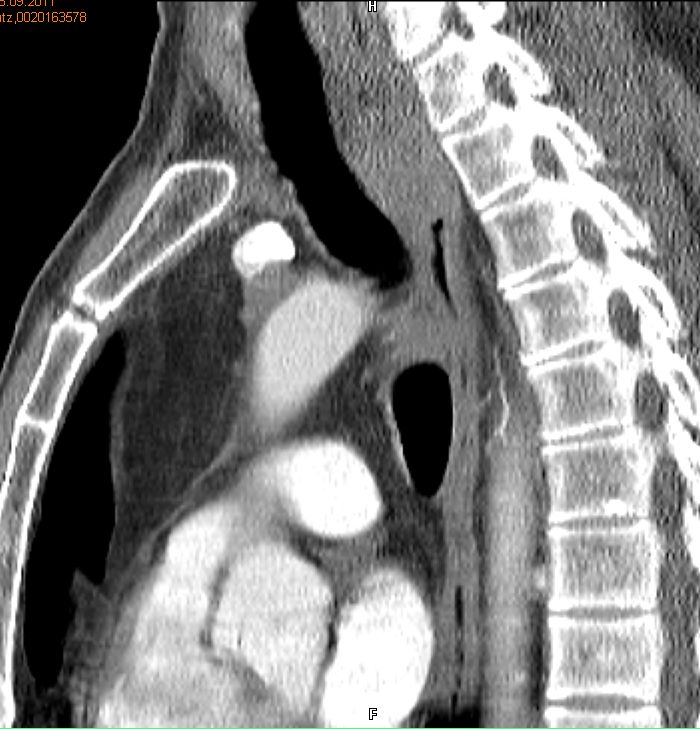

Rezidiv nach Radiochemotherapie eines kleinzelligen Tracheakarzinoms mit großer supraclavikulärer Metastase | |||